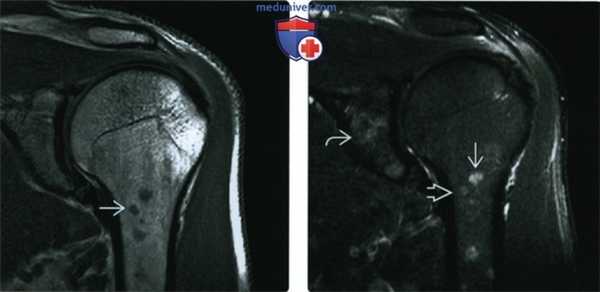

(Слева) МРТ Т1ВИ, коронарный срез: у мужчины 48 лет с неказеозными гранулемами левой плечевой кости, подтвержденными биопсией, определяются округлые и неровные интрамедуллярные образования. Они гипоинтенсивные, но немною гиперинтенсивны по отношению к мышцам.

(Справа) МРТ Т2ВИ, режим подавления сигнала от жира, коронарный срез: у этого же пациента определяются образования со слегка повышенной интенсивностью сигнала и ярким сигналом на Т2. Также отмечается поражение суставной впадины лопатки. При отсутствии клинической информации или данных биопсии дифференциальный диагноз с метастазами или множественной миеломой невозможен.